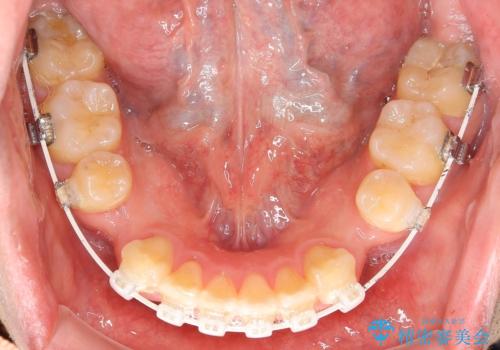

- 矯正装置

- 審美装置

抜歯する事で歯の移動量が大きいことからワイヤー表側矯正装置で治療を行うことになりました。

今回のような歯の移動量が大きい場合、インビザライン治療では歯が傾いてしまう場合があります。

ワイヤー治療では歯の傾きを抑えながら大きい距離の移動が可能で、かみ合わせが深くなるリスクも少ないです。